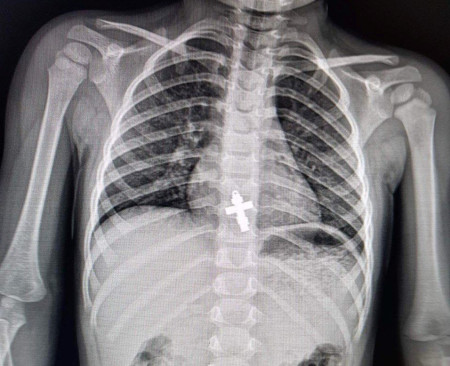

Як розповідає лікар-ендоскопіст та хірург дитячий Олександр Сльозко, проковтування монет дітьми – поширене явище. Такі випадки трапляються регулярно, подекуди й до 10 на тиждень. У квітні лікарям також довелося ендоскопічно діставати з бронхів підлітків цвях та канцелярську кнопку, а зі стравоходу дворічної дитини – натільний хрестик.